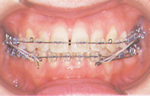

5. 治療開始

矯正歯科治療は、動的治療と静的治療(保定)の二段階に分かれています。

(1)

治療計画に従い、いろいろな矯正装置を使って歯を動かし、段階的に治療を始めます。

(2)

上下の歯が計画どおりに動いて、次第に正常なかみ合わせになると最終段階で仕上げの治療をします。